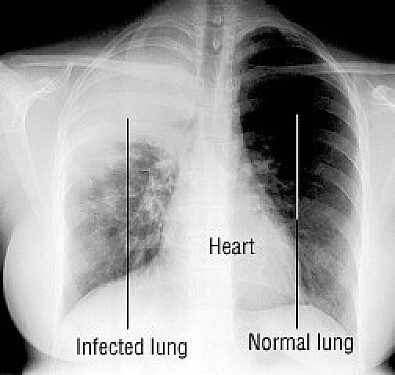

ممکن از ریهها با اشعه ایکس عکسبرداری شود و برای اطمینان از عدم وجود بیماریهای دیگر، آزمایش خون انجام شود.